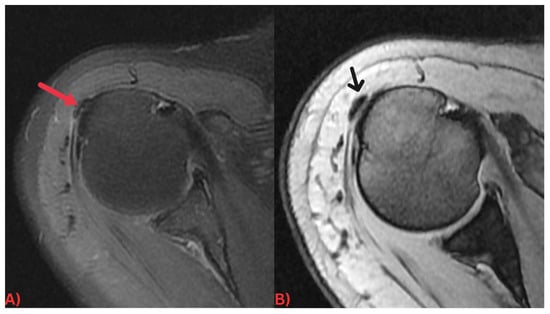

Specifically, MRI images display hydroxyapatite deposits as regions with low signal intensity across both T1- and T2-weighted images, attributable to the high mineral content of hydroxyapatite, a form of calcium phosphate crystals [27]. Consequently, this results in its manifestation in MRI images (Figure 3). Concurrently, MRI also reveals inflammation signs within surrounding soft tissues, such as edema and increased signal intensity on T2-weighted images [28] (Figure 4). Edema, a common response to inflammation or injury, indicates the body’s reparative efforts, while a heightened signal intensity on T2-weighted images typifies inflammation and is present in several conditions, including HADD (Figure 5).

Figure 3. (A) Axial T2 fat-saturated MRI image and (B) sagittal PD fat-saturated MRI image of the left hip demonstrating a well-defined low signal intensity calcification at the insertion of the left gluteus medius tendon (red arrows) with surrounding soft tissue edema.